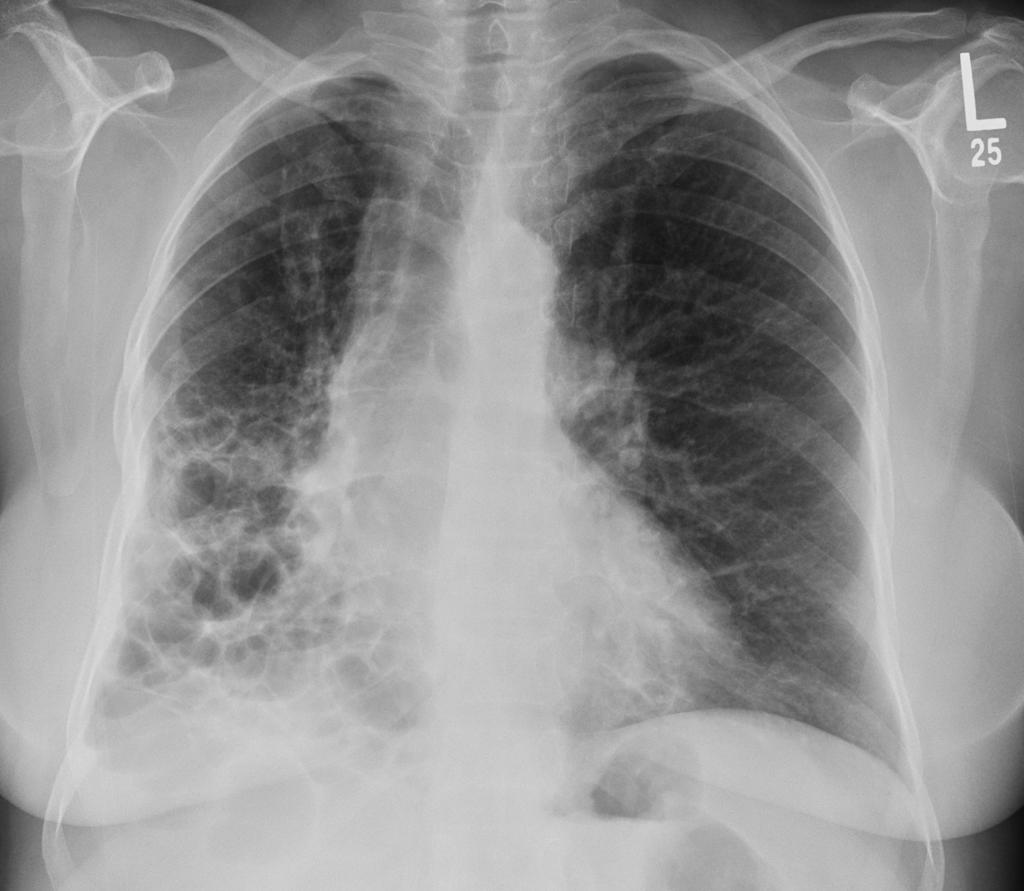

间质性肺疾病的诊断方法与标准

你是不是也有过这样的经历:咳嗽了好几个月,各种止咳药都试过了,但就是不见好转?或者爬个楼梯就气喘吁吁,家人都说你是缺乏锻炼,但你心里总觉得哪里不对劲? 如果这...